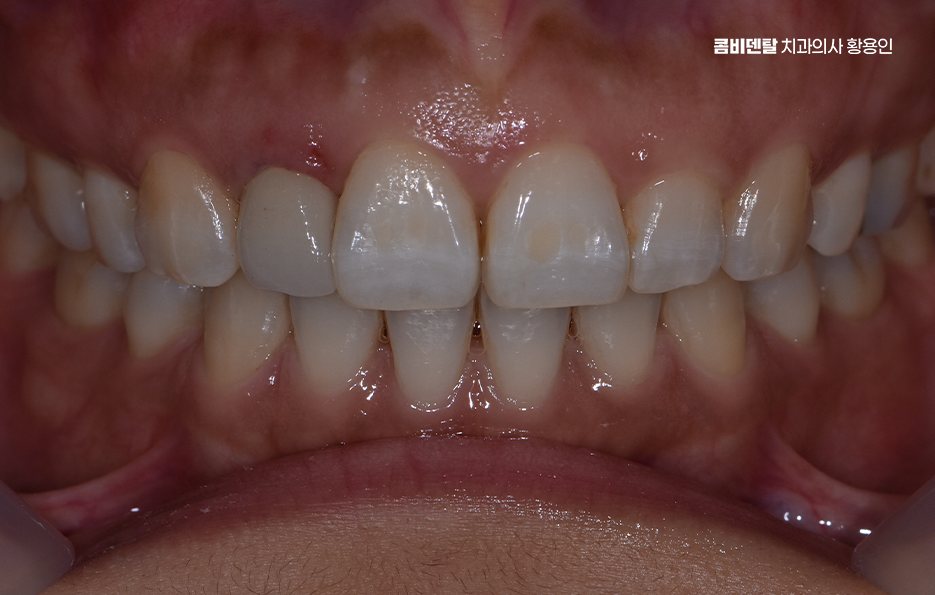

앞니는 사람의 얼굴에서 먼저 눈에 띄는 부위이기 때문에 심미적인 부분이 아주 중요한데 충치가 심하거나 깨지거나, 색이 변해버린 앞니를 그냥 두기에는 부담스럽고, 치료를 하더라도 주변 치아와 똑같이 자연스럽게 보여야 하다보니 이런 앞니에 적합한 보철치료 방법이 바로 앞니 올세라믹 크라운 치료라고 할 수 있어요

올세라믹이라는 건 말 그대로 금속이 전혀 들어가지 않은 순수 도자기 재질로 만들어진 보철물을 말하는데 금속이 없기 때문에 빛이 투과되는 방식이나 색상의 자연스러움이 실제 치아와 거의 흡사해서, 앞니처럼 시선이 집중되는 부위에 사용하면 주변 치아와의 경계가 거의 티 나지 않게 복원이 가능하며 특히 사진 찍을 때나 밝은 빛 아래에서도 회색 그림자나 반사광이 없기 때문에 심미적인 치료가 가능하다고 볼 수 있어요

앞니 올세라믹 치료는 과정을 살펴보면 우선 정확한 진단이 필요한데 현재 치아 상태가 올세라믹으로 치료 가능한지, 신경치료가 필요한지 여부와 치아 삭제량은 어느 정도로 해야 하는지 등을 평가하며 특히 앞니는 단순히 하나의 치아만 보지 않고, 양옆 치아와의 길이, 색상, 형태, 그리고 웃을 때 보이는 ‘스마일라인’까지 함께 고려해야 하기 때문에, 치료를 하기 전에 충분한 상담과 앞니 올세라믹의 특징에 대한 올바른 이해가 필요한 거예요

앞니 올세라믹 마지막 단계는 완성된 올세라믹 크라운을 치아에 접착하고, 교합을 조정하는 마무리 단계로 이때 중요한 건 주변 치아와 얼마나 조화롭게 어우러지는지를 보는 거예요. 색상은 단순히 ‘흰색’ 하나로 결정되는 게 아니라, 투명도, 밝기, 색조까지 섬세하게 조정돼야 하고 특히 앞니는 음식을 자르거나 말할 때 중요한 기능을 하기 때문에, 교합, 즉 맞물림이 정확해야 장기간 사용할 수 있어요.